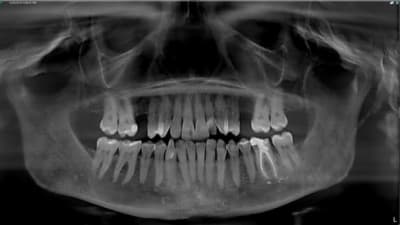

Continuing Education CE Articles Digital Imaging Let There Be Light By Cornelia Cone, MA, Miles Reed Cone, DMD July 01, 2019